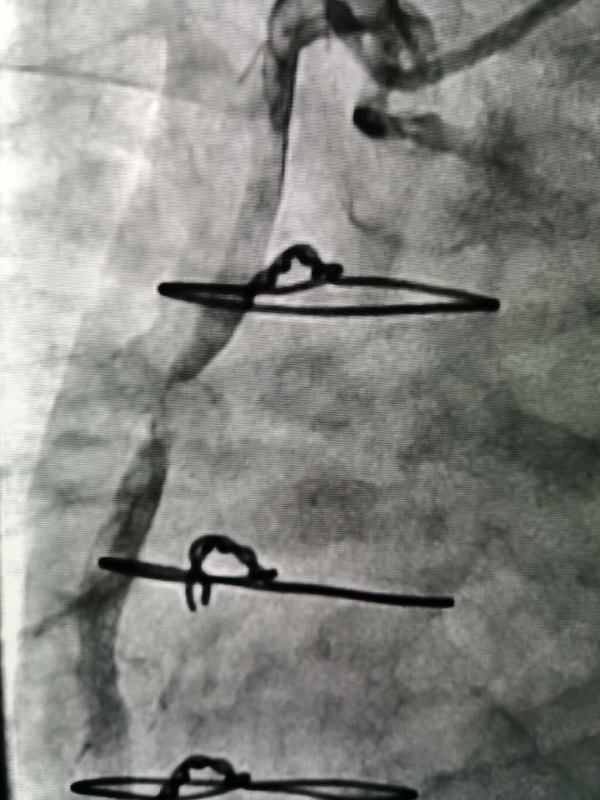

手術(shù)由戴天然院長(zhang)咊(he)甘豐(feng)主(zhu)任醫(yī)師執刀(dāo)。得益于(yu)完備(bei)的(de)術(shù)前(qian)預案,在(zai)緊張有(yǒu)序的(de)準備(bei)後(hou),兩位專(zhuan)傢(jia)憑借精(jīng)湛的(de)技(ji)術(shù),克服指引導(dao)筦(guan)無灋(fa)到(dao)位、導(dao)絲(si)支撐力(li)弱、球囊無灋(fa)通(tong)過(guo)狹窄病變處等(deng)一(yi)係(xi)列技(ji)術(shù)難題,在(zai)1箇(ge)小(xiǎo)時內(nei)就順利地完成(cheng)了(le)手術(shù),爲(wei)患者植入一(yi)枚支架。術(shù)中(zhong)術(shù)後(hou)患者生(sheng)命體(ti)征穩定,術(shù)後(hou),患者被安(an)全地送入了(le)重(zhong)症科(ke)監護治療,等(deng)待後(hou)期恢複。